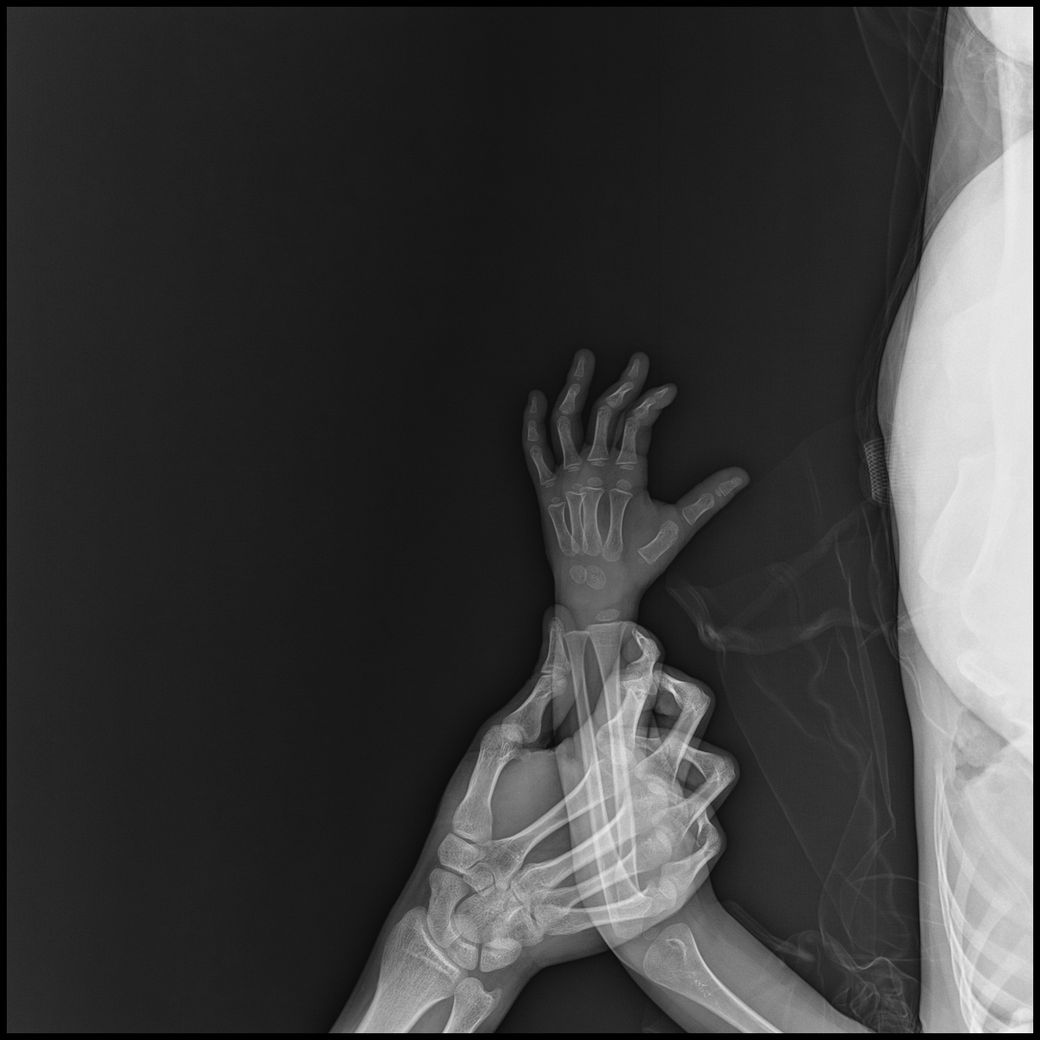

고관절,복부일부,생식기등 민감부위등이 추가로 촬영되었고

원본영상을 보니 몸통이 다찍혀서 피폭량 걱정으로 아무것도 못하고 있고

- 몸통일부+손같이찍힘 : 6장

• 3번 째 사진